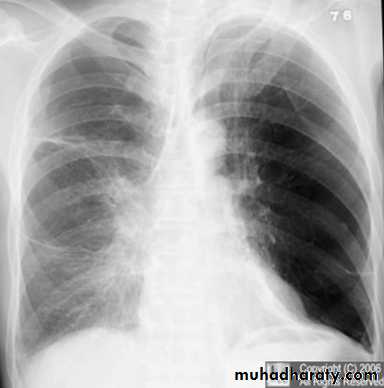

Tension pneumothorax.

On a posteroanterior chest x-ray (A), the left hemithorax is very dark or lucent because the left lung has collapsed completely (white arrows).

The tension pneumothorax can be identified because the mediastinal contents, including the heart, are shifted toward the right, and the left hemidiaphragm is flattened and depressed. A computed tomography scan done on a different patient with a tension pneumothorax (B) shows a completely collapsed right lung (arrows) and shift of the mediastinal contents to the left.

Tension Pneumothorax. Portable chest film in a 43-year-old woman with ARDS shows a large right pneumothorax with mediastinal shift and ipsilateral diaphragmatic depression, suggesting tension.

Air was evacuated under pressure during emergent placement of a right chest tube.